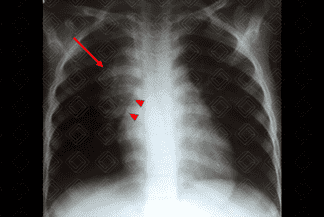

Texto alternativo para a imagem Figura 3. Créditos: Dra Elazir Mota - Rio de Janeiro/RJ

Estudo foi complementado com tomografia computadorizada do tórax, após a administração do contraste venoso: cortes coronal (figura 2) e sagital (figura 3), evidenciando linfonodomegalias mediastinais com realce periférico pelo meio de contraste e conteúdo interno hipodenso, não captante do meio de contraste (setas brancas), devendo representar áreas de necrose. Este aspecto tomográfico das linfonodomegalias, com área central de necrose, é muito sugestivo de doença granulomatosa, especialmente tuberculose.